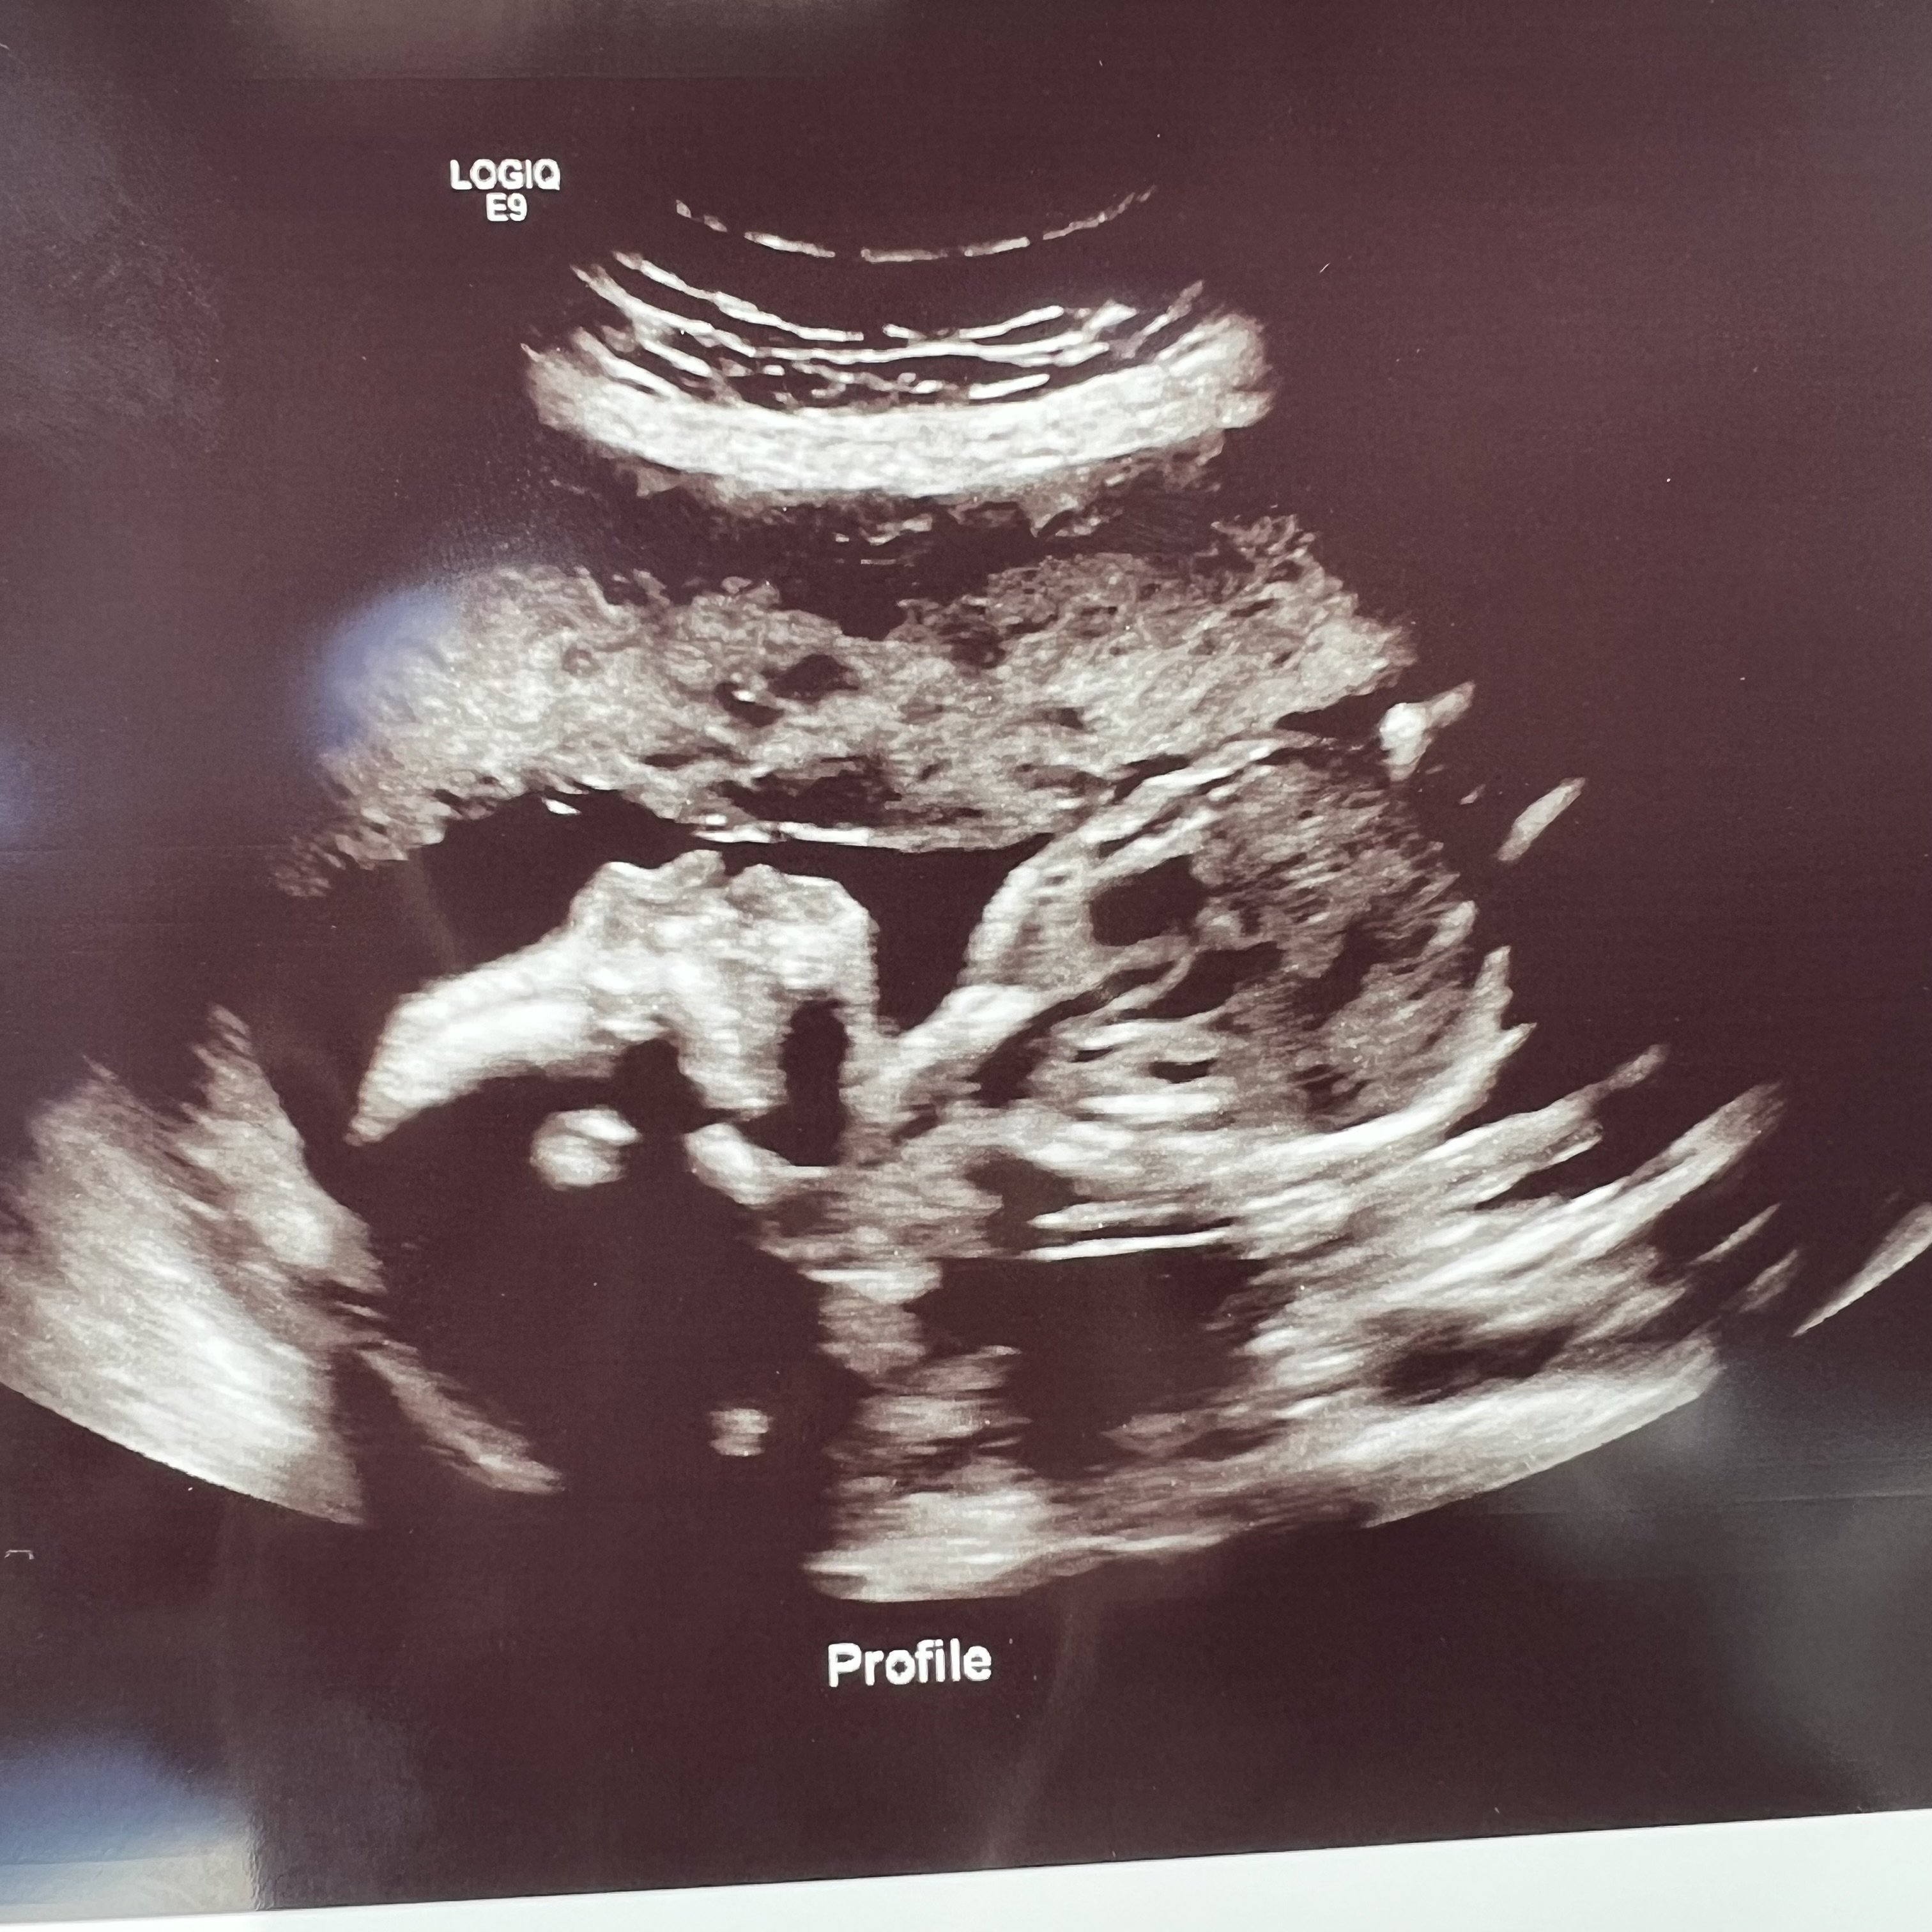

20 weeks 👶🏽🩵

Due 10/31/2023